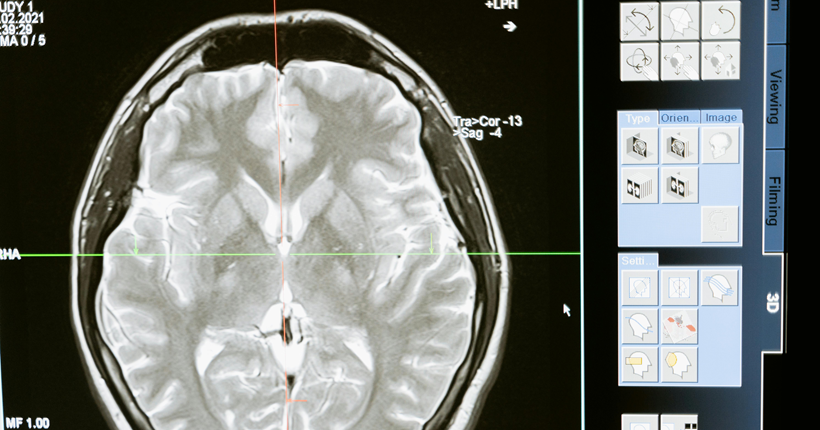

El dolor representa un problema no resuelto en las personas mayores, particularmente en aquellas con demencia. Debido al envejecimiento poblacional, y la asociación de esta patología neurodegenerativa con la edad, actualmente observamos un incremento en este grupo de pacientes. Además, las personas con demencia son más propensas a experimentarlo debido a la coexistencia de deterioro cognitivo con otras entidades clínicas de tipo crónico. A su vez, la dificultad para expresarlo de forma verbal que presentan estas personas, como resultado de la evolución de la demencia, acentúa la complejidad del abordaje del dolor, materializándose esta, específicamente, en que la valoración del dolor en personas con deterioro cognitivo es, a menudo, inadecuada.

La imposibilidad de autoreporte de la experiencia dolorosa propia de los pacientes con demencia avanzada impide la utilización de los autoinformes, instrumentos considerados como la medida más fiable y afinada para contrastar la existencia e intensidad del dolor siempre que la persona no presente dificultades de comunicación y/o sea capaz de recordar, entender y responder sobre su experiencia dolorosa.

En este contexto, la observación conductual de la persona con demencia avanzada como alternativa para valorar el dolor a través del reconocimiento de cambios comportamentales ha conllevado a la confección de hasta 24 escalas, aunque no todas están disponibles en español por no haber sido adaptadas culturalmente y validadas a este idioma. Entre todas las escalas, la Pain Assessment in Advanced Dementia Scale (Painad), concretamente, por su sencillez y sus propiedades psicométricas, las cuales avalan su validez y fiabilidad, se postula como una herramienta prometedora para minimizar el infradiagnostico e infratatamiento del dolor en las personas con demencia.